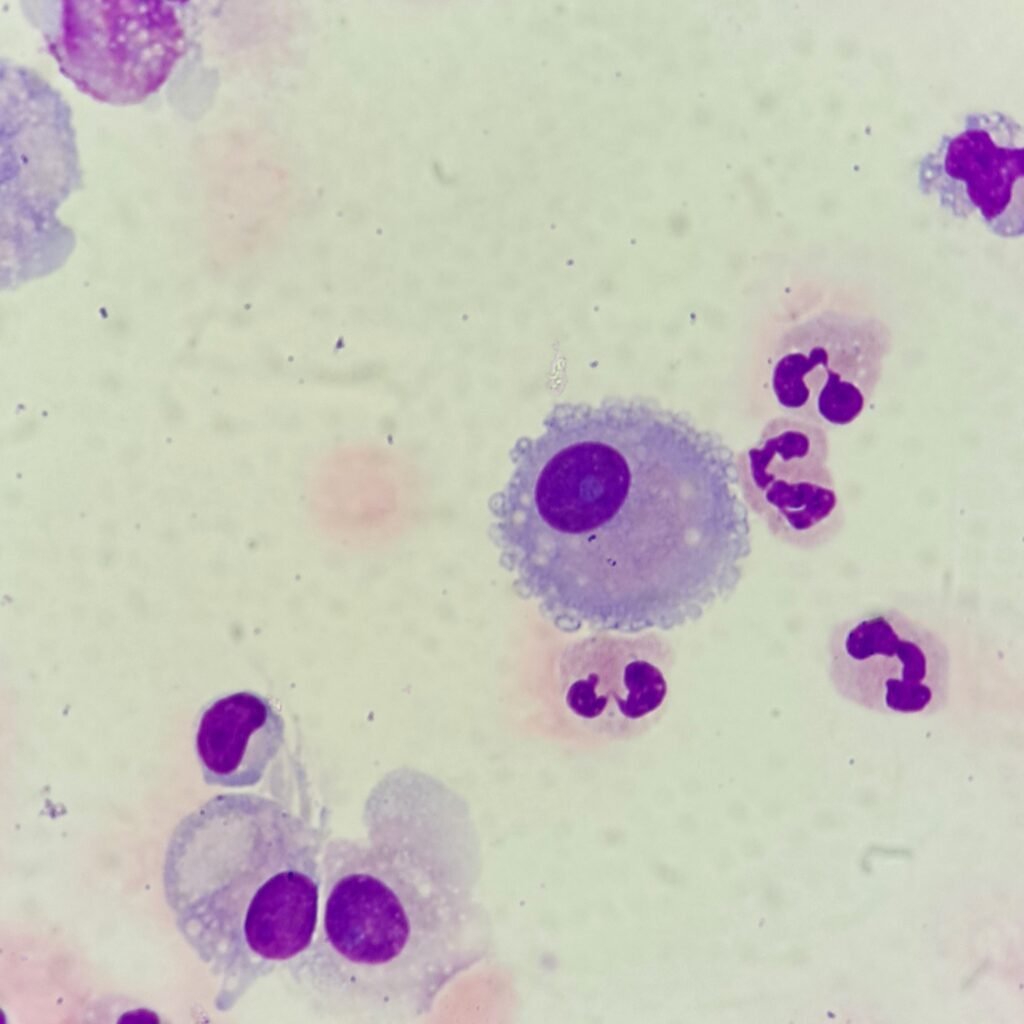

Mesothelial cells are described as having a “fried egg” appearance. They have a round to oval nucleus with smooth borders and evenly distributed chromatin. Nucleloli are usually present. Mesothelial cells may also be multinucleated.

Macrophages are about the same size as mesothelial cells, so the two can often be confused. Macrophages can usually be differentiated by the presence of vacuoles and a lacey chromatin. If both cell types are present and differentiation is difficult, take a look around the slide to get an idea of each kind of morphology before starting a differential.